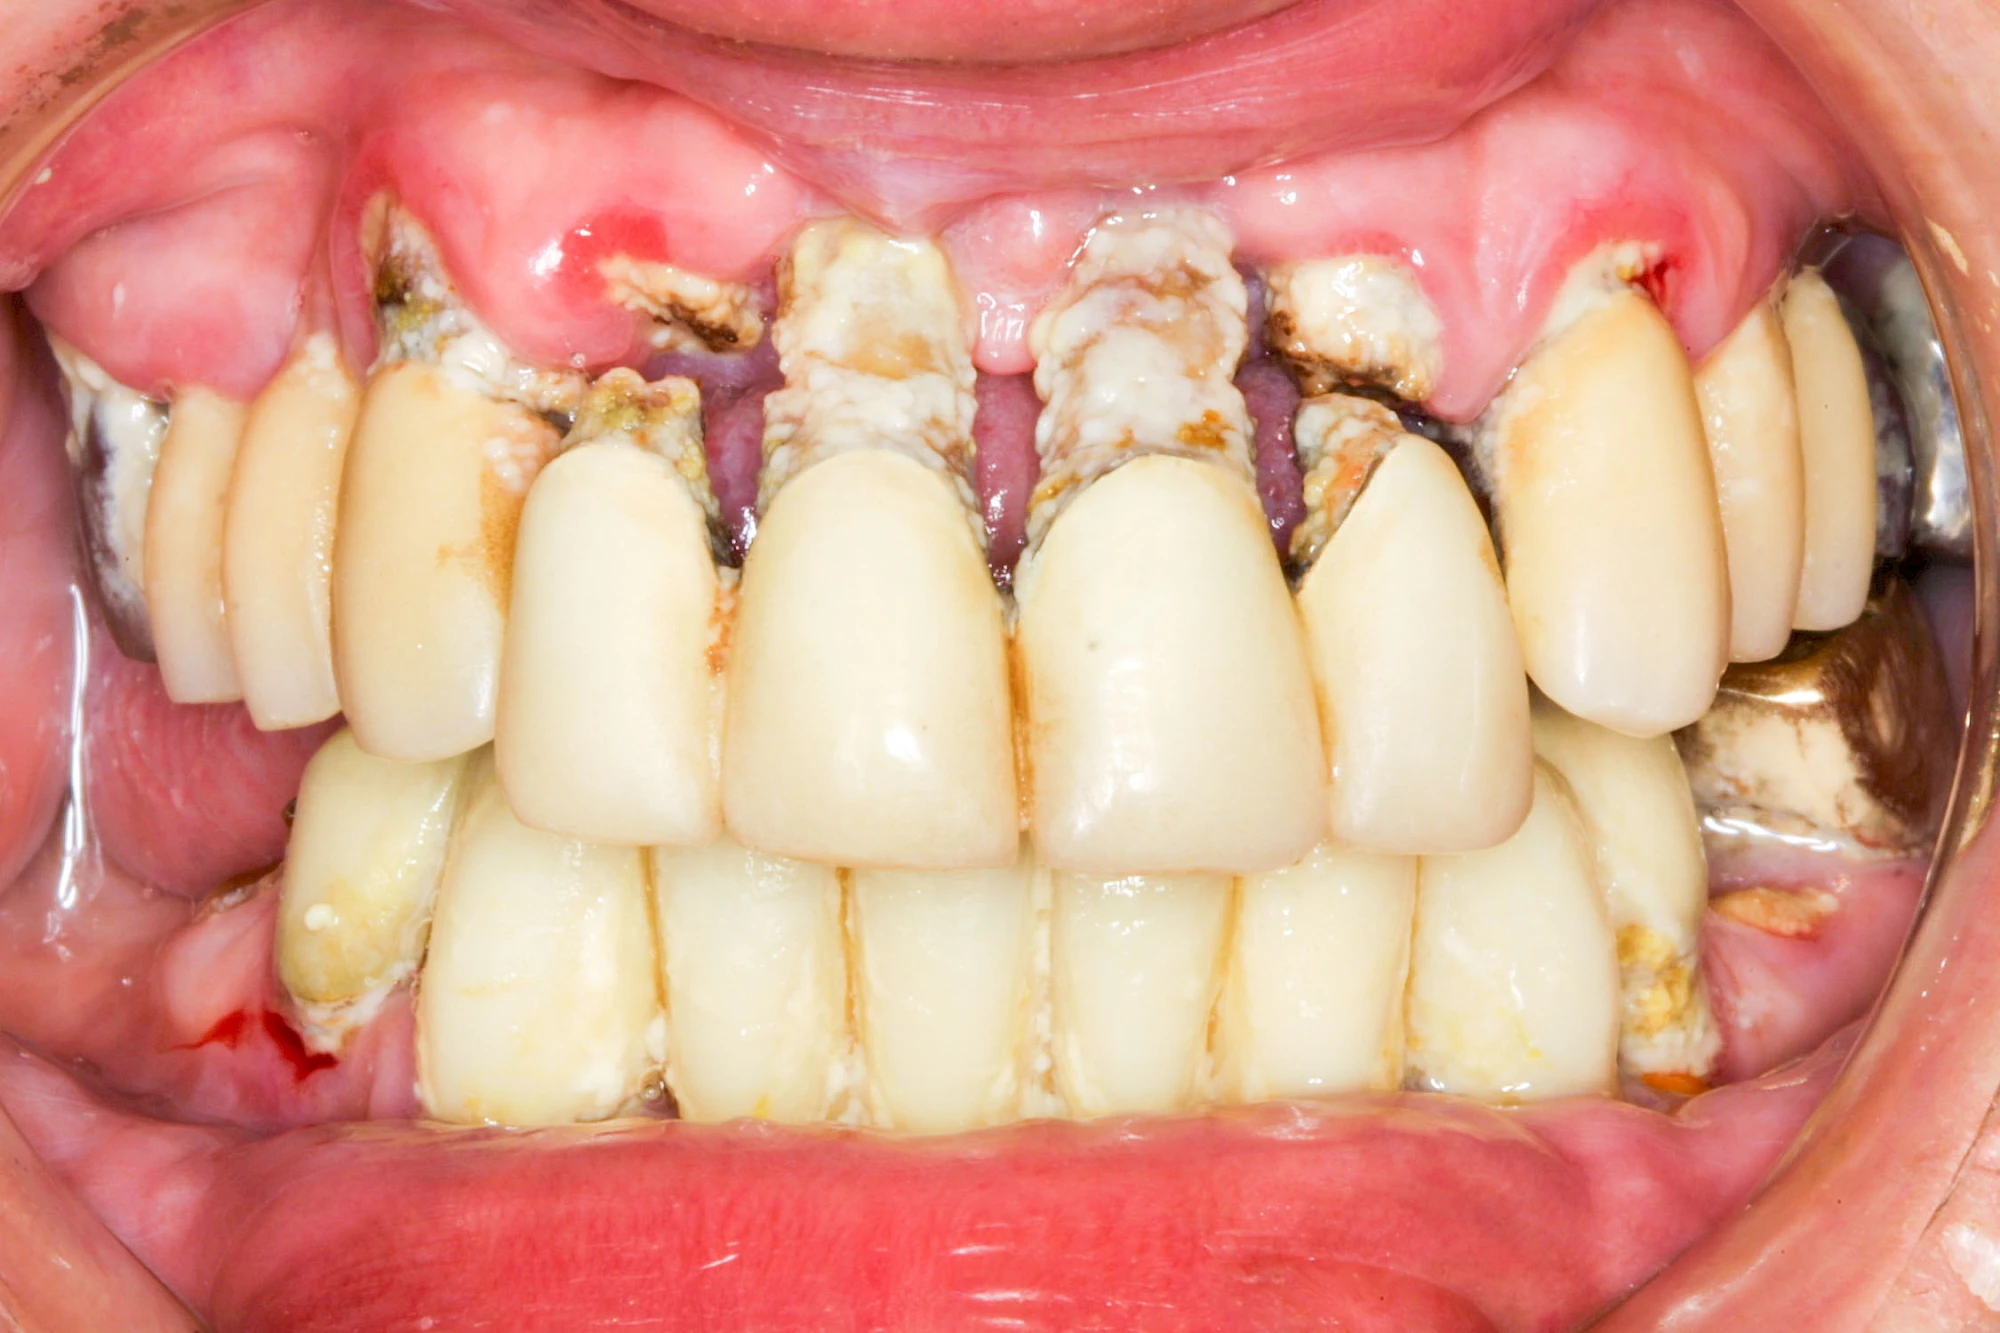

Ist zunächst nur das Zahnfleisch von der Entzündung betroffen, spricht man von Gingivitis. Später, wenn auch der Knochen um die Zähne herum entzündet ist, spricht man von einer Parodontitis. Bei der Parodontitis wird der Knochen nach und nach abgebaut und das Zahnfleisch zieht sich zurück. Die Zahnhälse und Zahnwurzeloberflächen liegen mehr und mehr frei. Die Zähne werden zunehmend lockerer und fallen schließlich aus.

Bakterien in den Zahnbelägen greifen neben den Zähnen auch das Zahnfleisch (Gingiva) und den gesamten Zahnhalteapparat (Parodont) an. Der Körper reagiert mit einer Entzündung, sichtbar als Rötung und Schwellung. Meist blutet das Zahnfleisch z .B. beim Essen oder auch beim Putzen der Zähne.